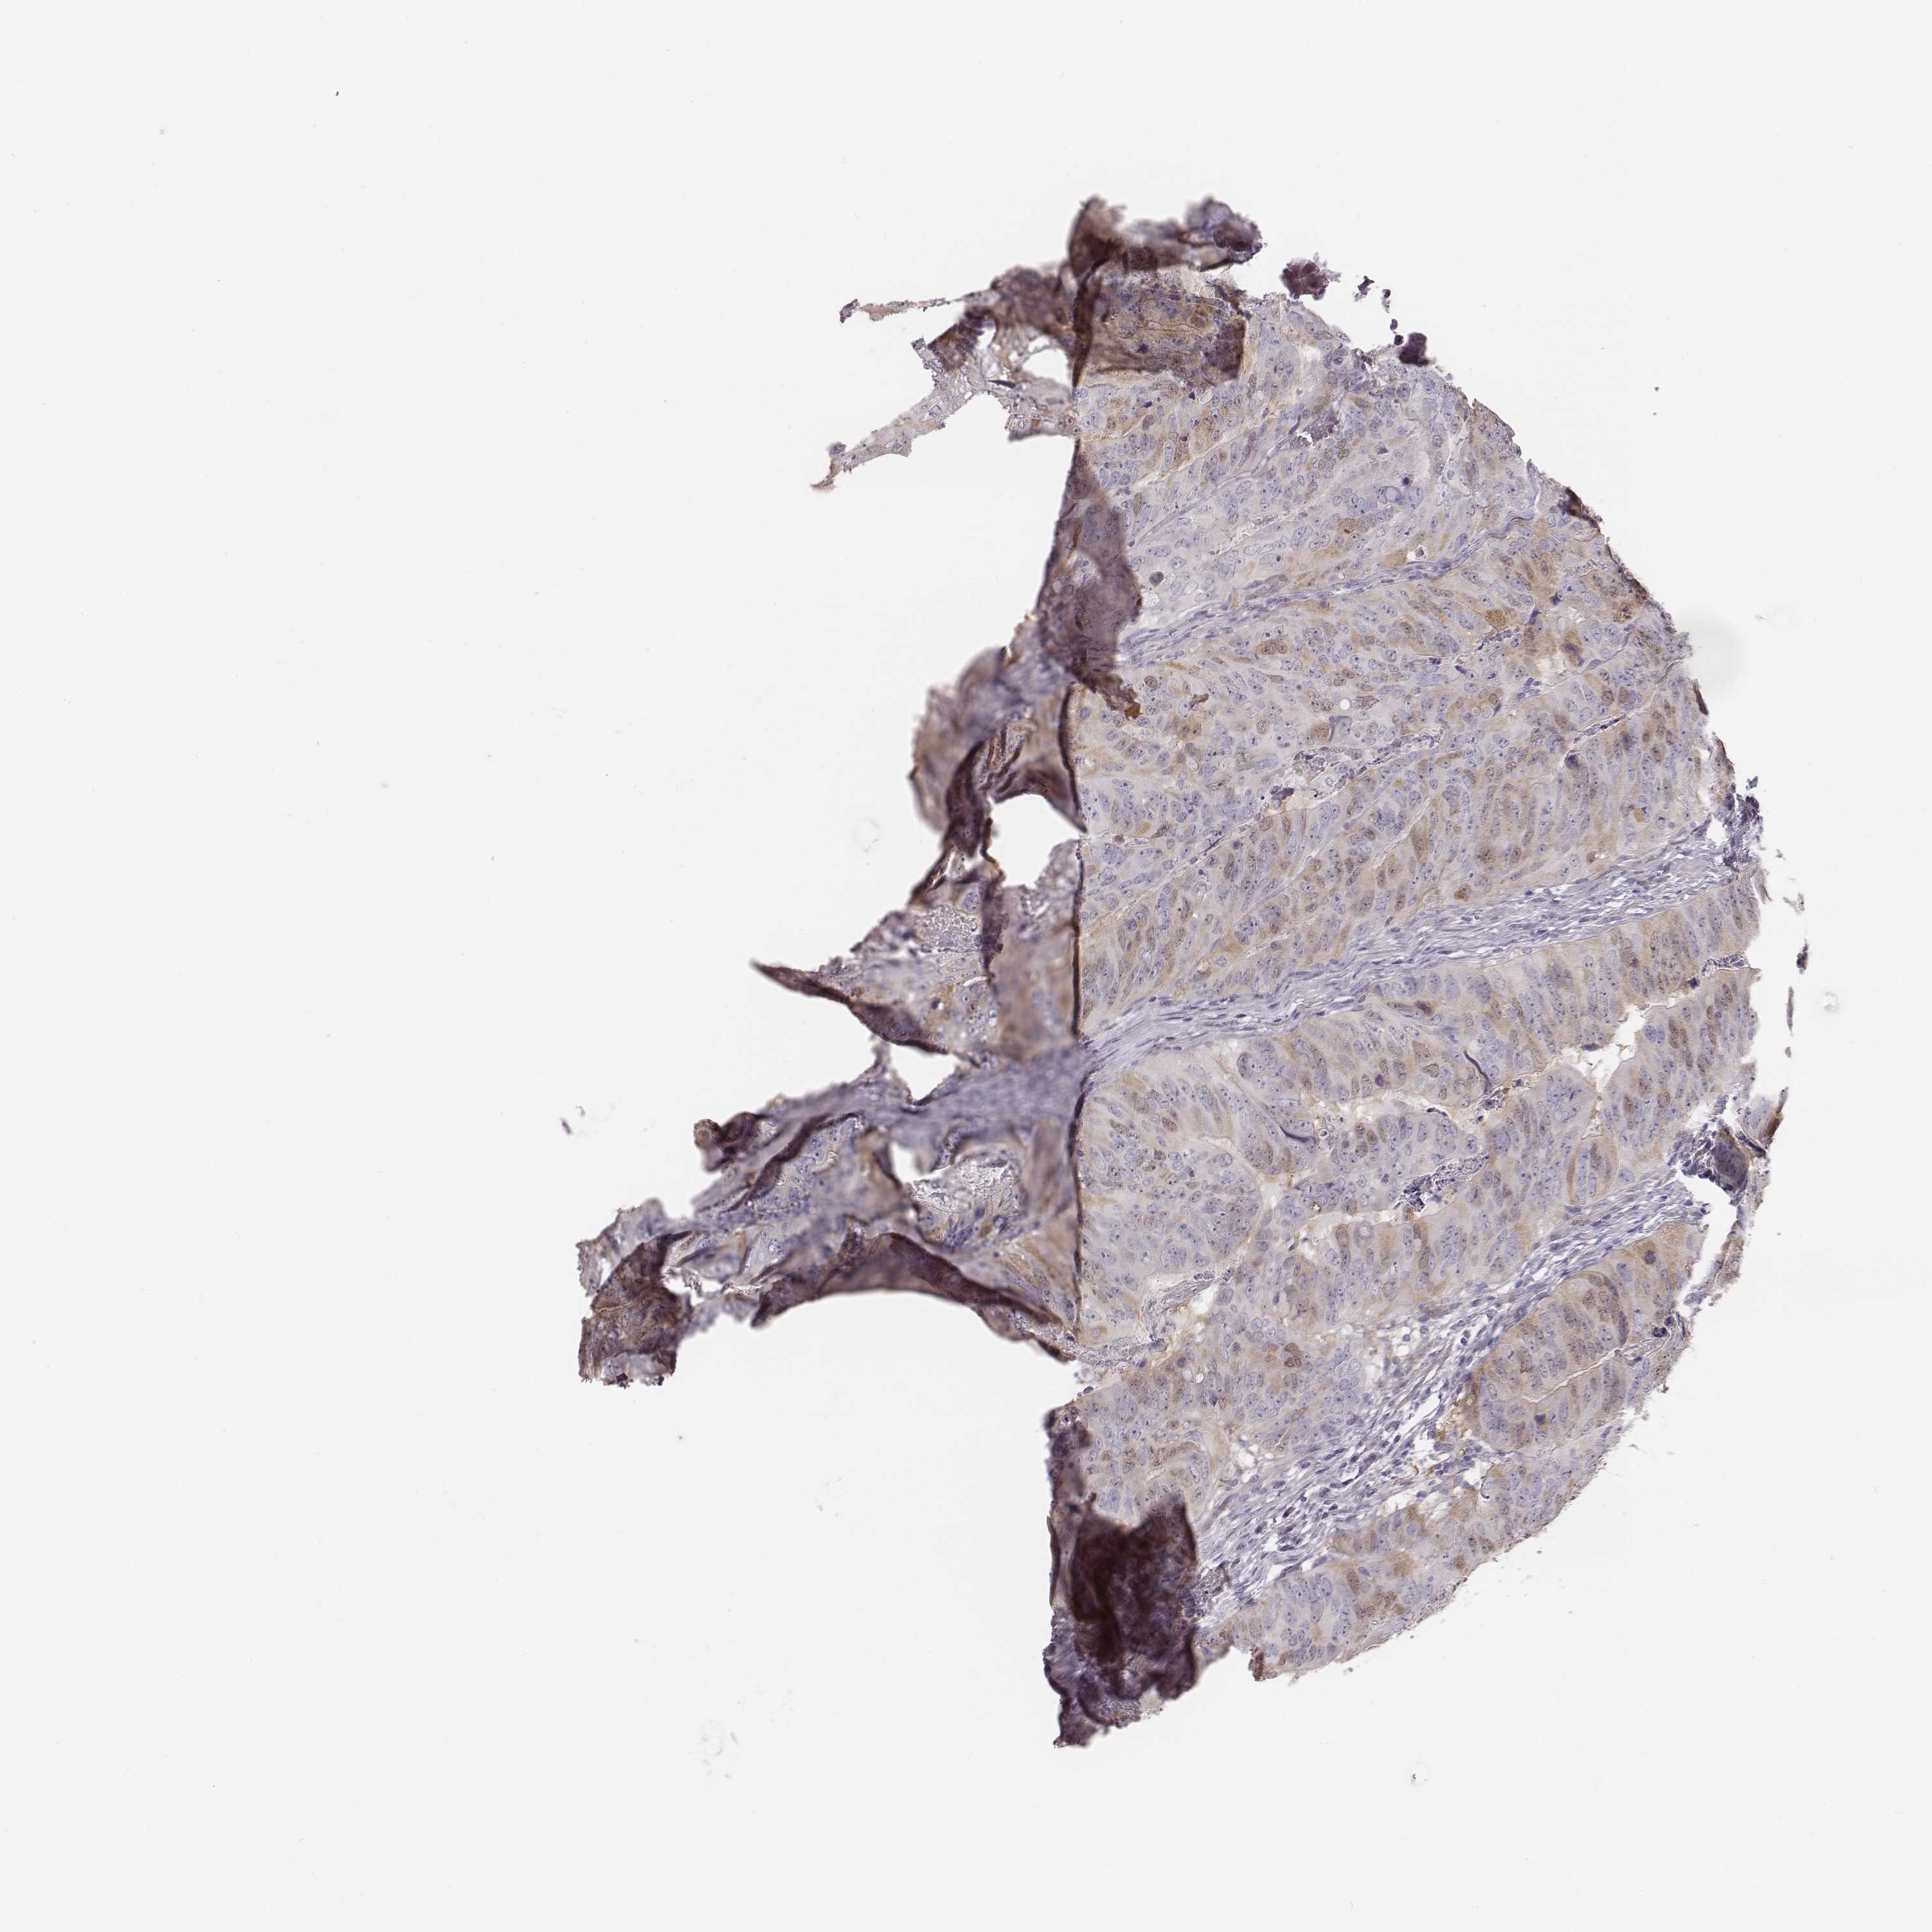

CANCER COLORECTAL CANCER Show tissue menu

Colorectal cancer

Human cancer

Colon adenocarcinoma